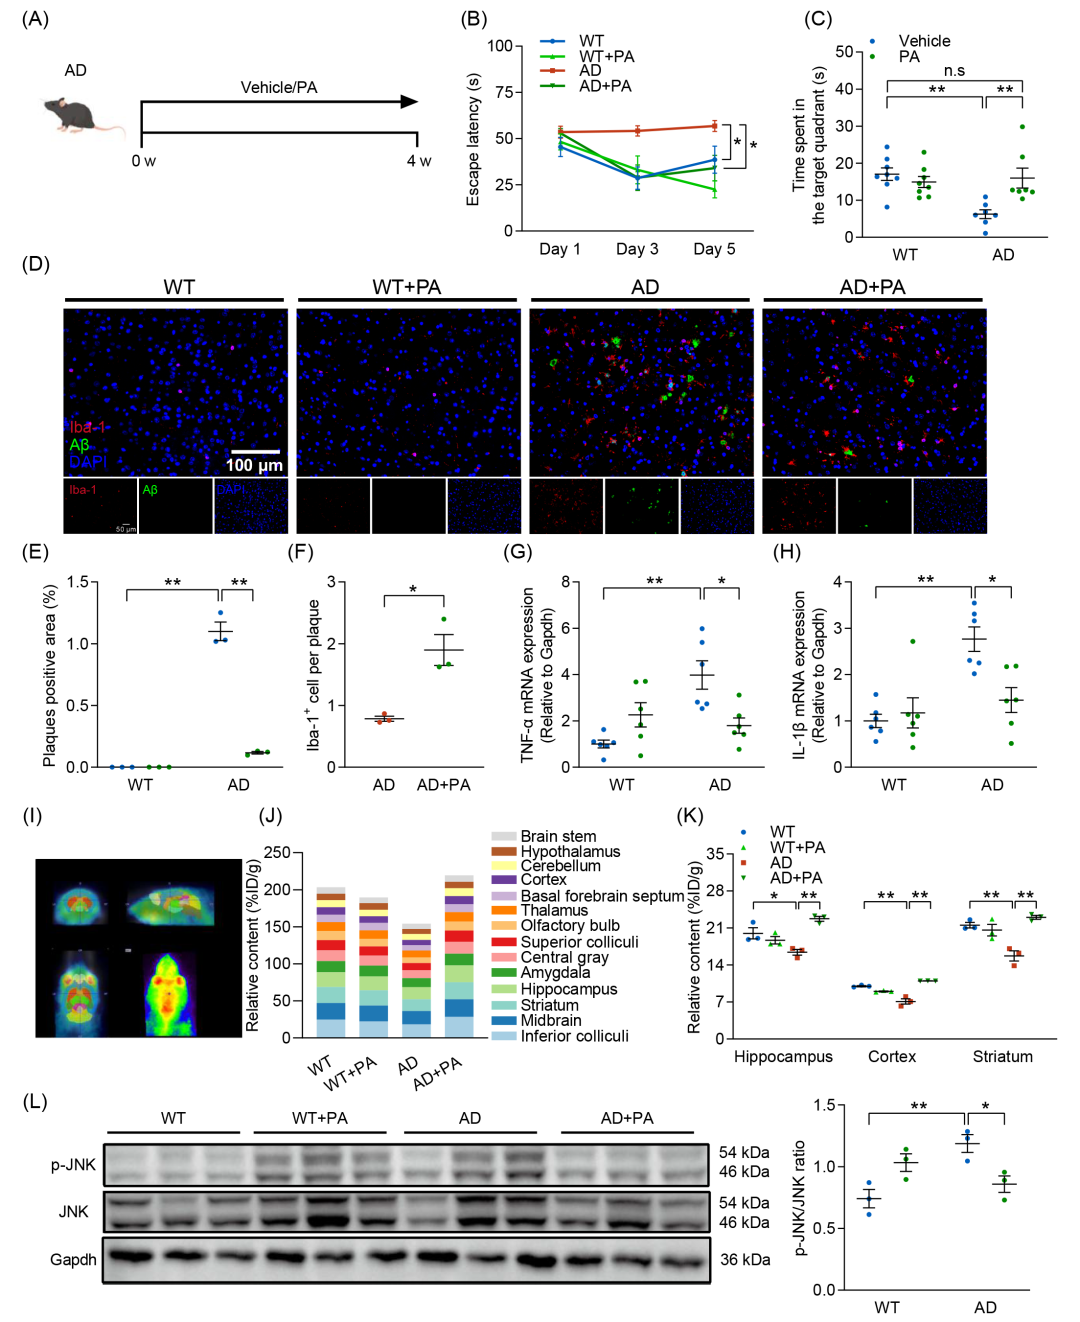

PA 穿透血脑屏障并改善认知能力

为了进一步证实PA在AD发病机制中的重要性,并研究PA对认知缺陷的治疗作用,使用丙酸钠对AD小鼠进行干预(图5A)。腹腔注射PA显著增强了AD小鼠的认知功能(图5B、C和图S7C),显著减少了脑内Aβ聚集,促进了小胶质细胞向斑块的募集,并增加了BDNF表达(图5D-F 和图S7E-I)。此外,PA干预降低了TNF-α和IL-1β水平(图5G、H)。为评估PA在AD小鼠脑中的穿透性及代谢情况,本研究利用正电子发射断层扫描(PET)成像进行追踪分析。PET成像显示PA可通过血脑屏障(图5I),其代谢主要集中在下丘、中脑、纹状体和海马等关键脑区(图5J、K)。PET定量分析进一步揭示,AD小鼠的PA代谢信号显著降低,尤以海马、皮质及纹状体区域最为明显,然而PA治疗可有效恢复这些信号(图5K)。已有研究表明,SCFAs通过上调FFAR3和抑制核因子κB(NF-κB)和c-Jun N末端激酶(JNK)的磷酸化发挥抗神经炎症作用。为进一步探讨PA增强的脑内代谢信号对神经炎症及Aβ沉积的影响,测定了NF-κB和JNK的磷酸化水平。结果发现,PA干预显著抑制AD诱导的JNK磷酸化,但对NF-κB磷酸化无显著影响(图5L和图S7L),最终下调β-分泌酶(BACE1)的表达(图S7K)。因此,PA可穿透血脑屏障,恢复AD小鼠脑内PA代谢紊乱,并通过抑制JNK磷酸化和上调BDNF表达,改善认知损伤和减缓AD病理进展。

图5. 丙酸(PA)补充改善AD小鼠的认知功能损伤

(A)每组接受PA或生理盐水干预的实验流程示意图;(B)逃避潜伏期(n = 7-8);(C)目标象限的停留时间;(D)小鼠皮层中Aβ沉积(绿色)及Iba-1+阳性小胶质细胞(红色)的免疫荧光染色图像(n = 3)(比例尺:100 μm);(E)Aβ斑块阳性区域的定量分析;(F)Aβ斑块相关小胶质细胞的定量分析;(G)TNF-α的mRNA水平测定(n = 6);(H)IL-1β的mRNA水平测定(n = 6);(I)轴位、矢状位和冠状位正电子发射断层扫描(PET)图像,显示PA在脑中的摄取情况;(J)脑中[18F]-FPA的摄取水平(%ID/g)(n = 3)(K)海马、皮层和纹状体[18F]-FPA的PET定量分析。(L)Western blot分析p-JNK和JNK蛋白表达水平(n = 3)。数据以均值 ± SEM表示。*p < 0.05,**p < 0.01;two-way ANOVA结合Tukey多重比较检验。